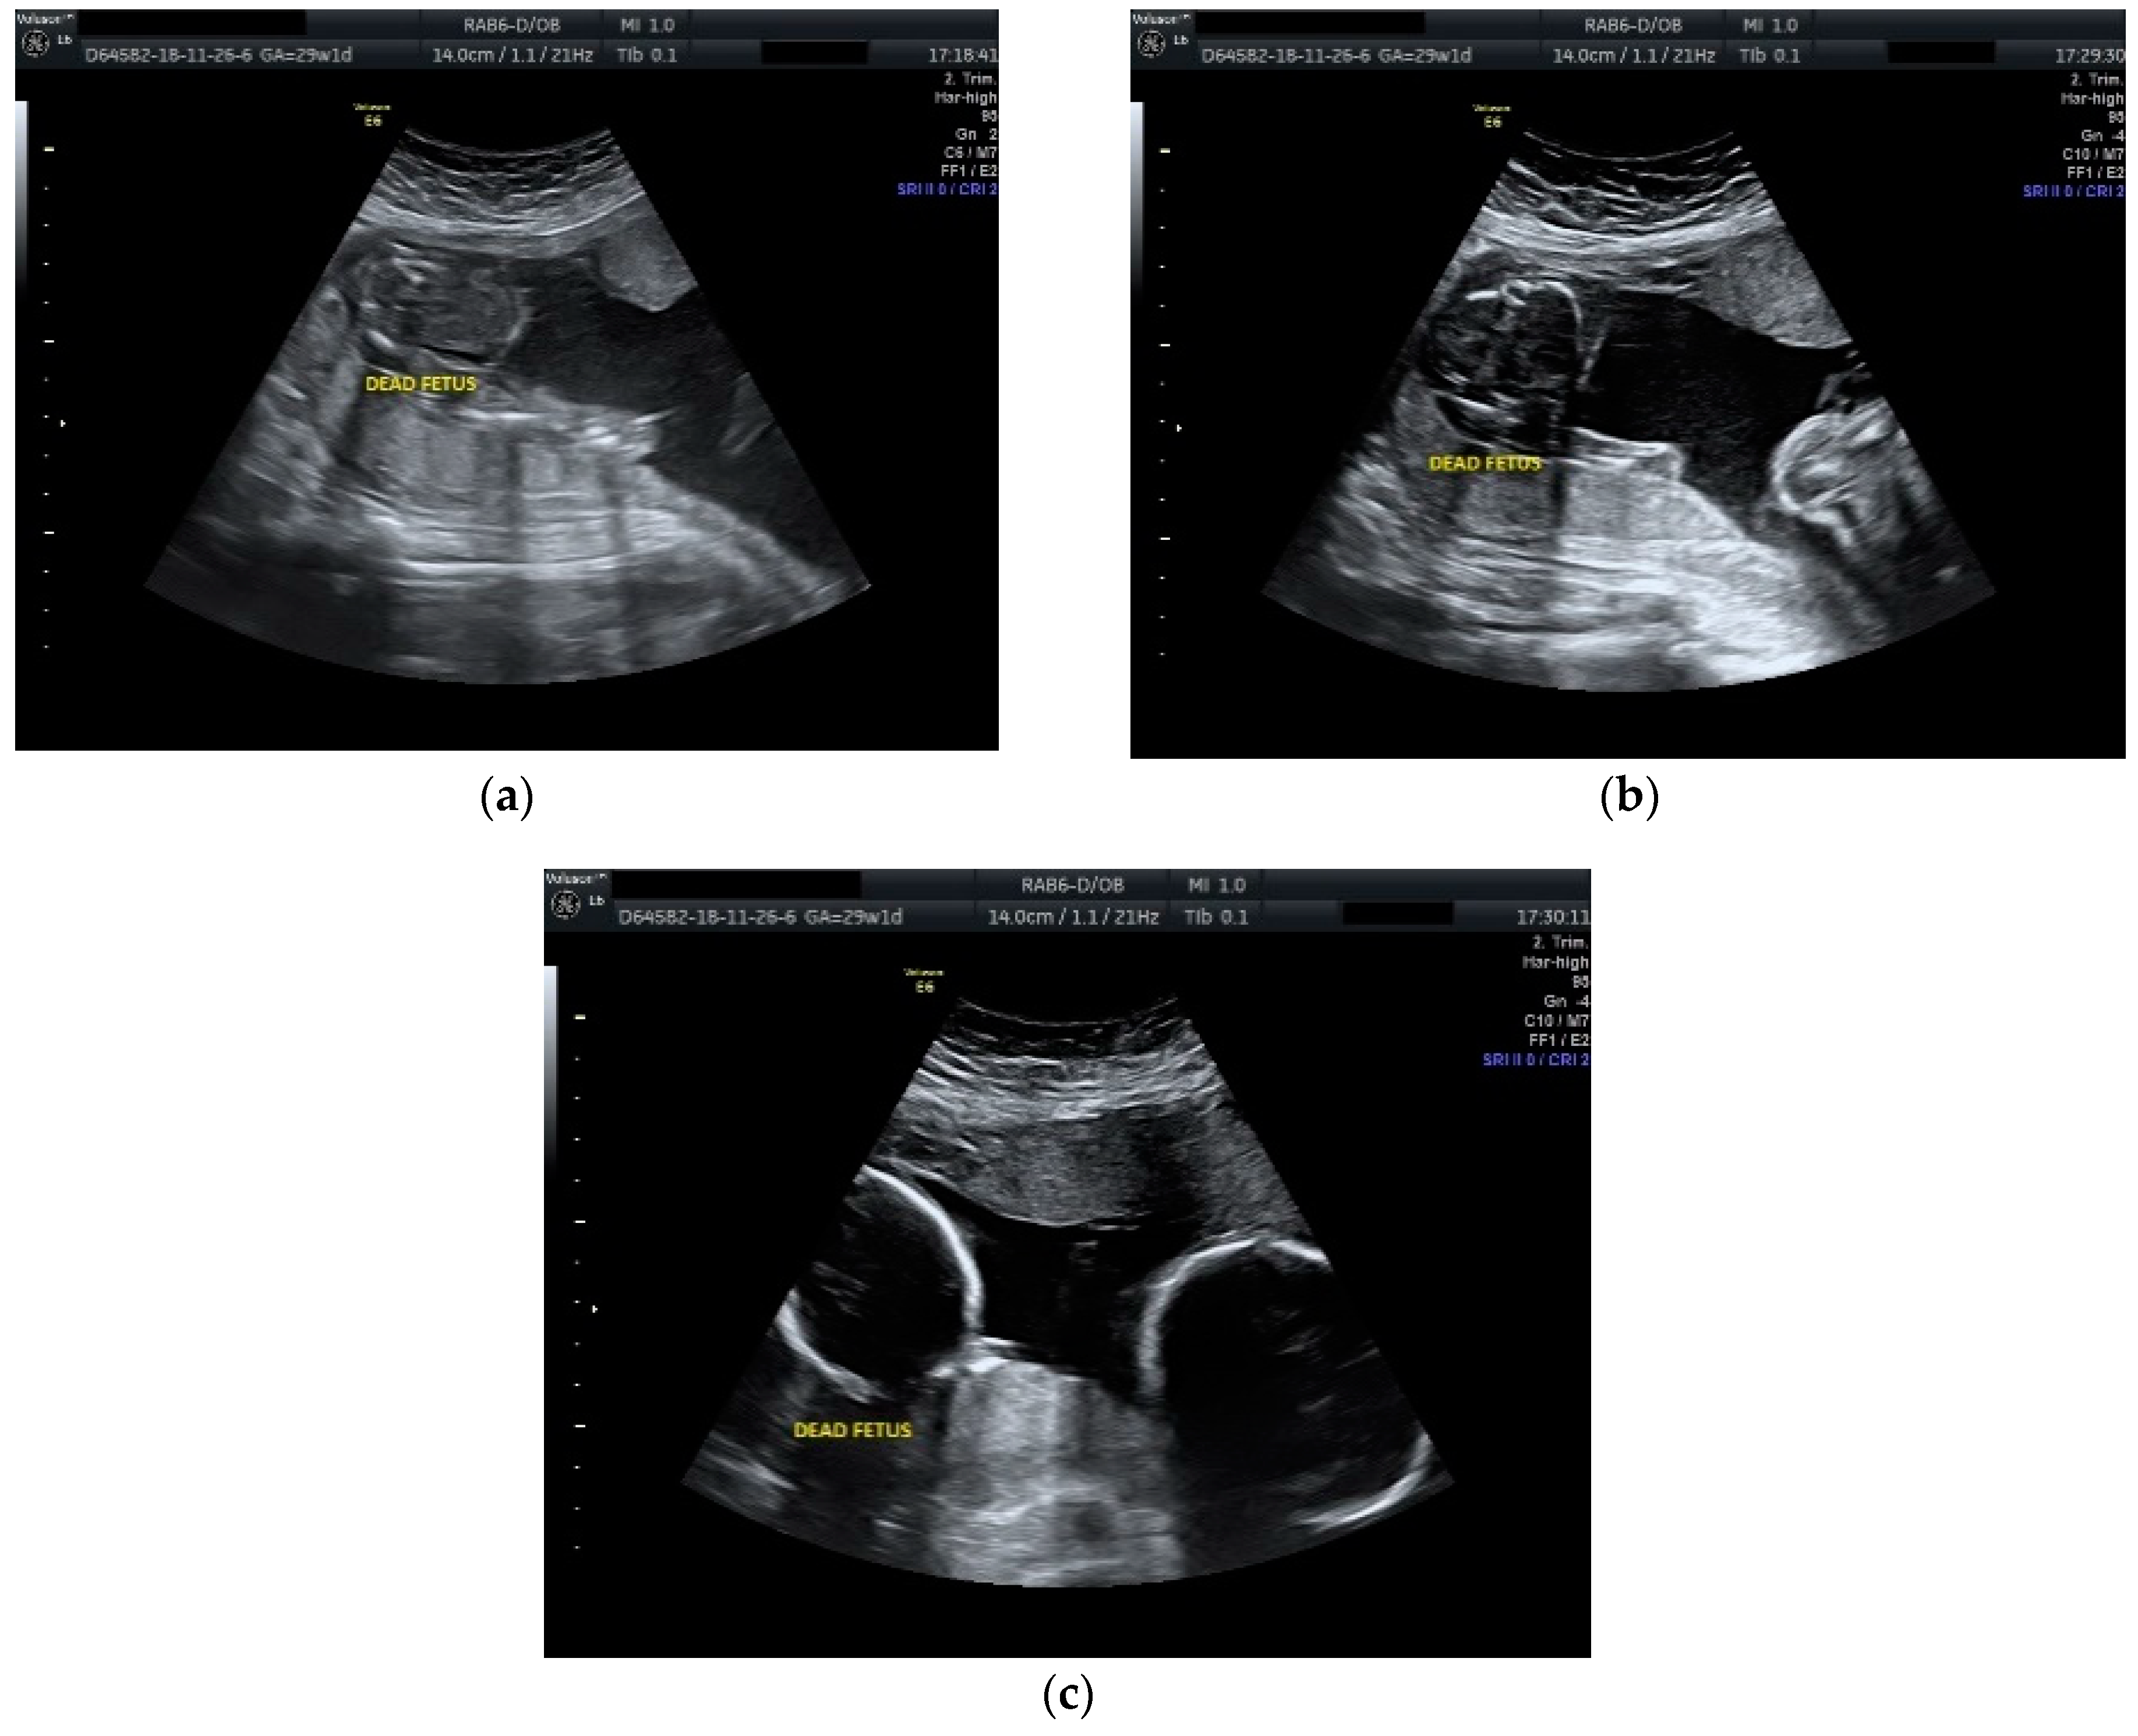

The case was managed conservatively with regular monitoring of the maternal coagulation profile, along with intensive fetal surveillance for the surviving twin (Figure 2 and Figure 3).

Figure 2.

Ultrasound scan performed at 29 weeks and 1 day of gestation: (a), (b) dead fetus along with normal growing fetus with normal amniotic fluid; (c) cephalic extremities of the two fetuses with evident growth discordance.